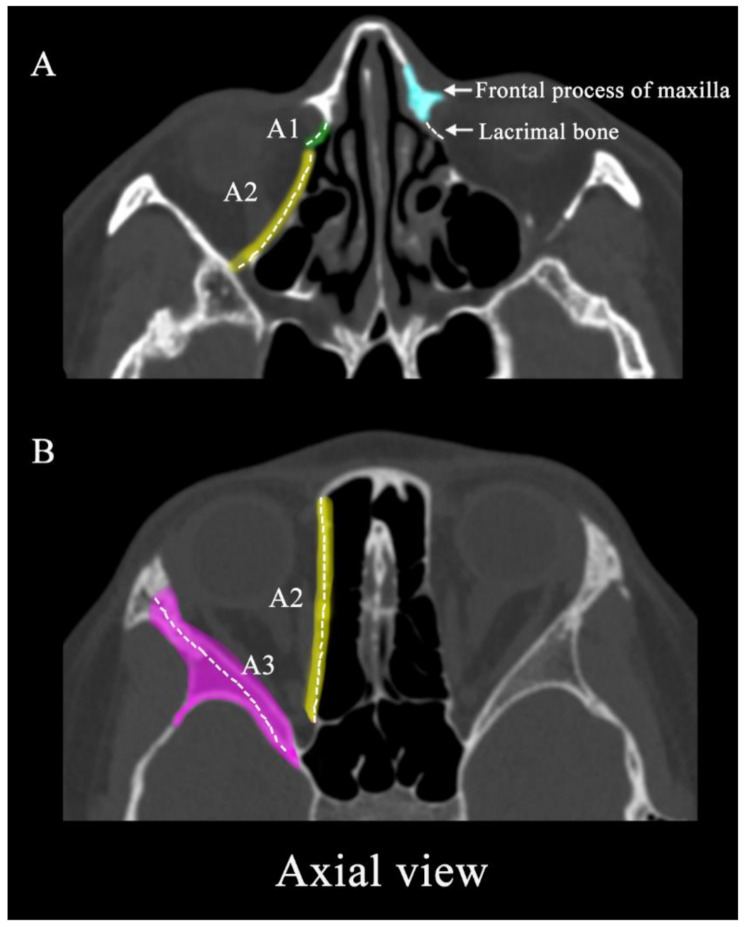

Methods: We retrospectively analyzed clinical and imaging data from 155 patients who experienced orbital fractures at our center between 2021 and 2023. Orbital fracture sites were classified as C/S/A according to imaging: the lacrimal bone was named as A1, the bony structure behind lamina papyracea as A2 and the lateral wall of the orbit (including the zygomatic bone and the greater wing of sphenoid) was appointed as A3 in the axial view; the orbital floor was divided into three equal parts as S1-S3 in the sagittal view; the frontal process of maxilla was designated as C1, the intermediate central midface between frontal process of maxilla and zygomaticomaxillary suture as C2 and the structure between the zygomaticofrontal suture and the zygomaticomaxillary suture was named as C3. First, we examined clinical characteristics, including age, gender, fracture position, as well as follow-up data on fracture location and diplopia duration. Next, we assessed the correlation between orbital fracture location (C/S/A) and diplopia occurrence. Lastly, we used a multivariable logistic regression model to evaluate predictors associated with the occurrence and location of diplopia in orbital fractures.